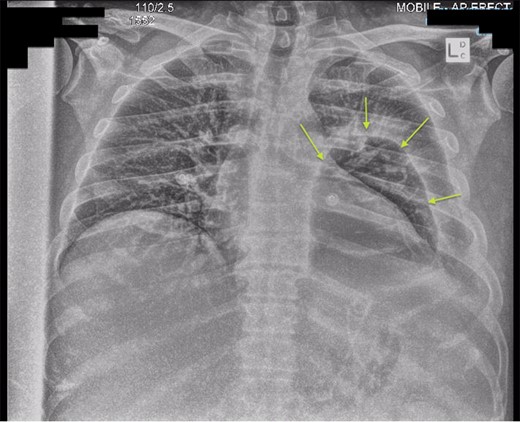

Chest X-ray in ICU following drainage showed what was thought to be Pneumomediastinum (Figs 1 and 2), and given this concern he was referred to the Cardiothoracic service. Subsequent CT suggested a large loculated hydro-pneumothorax, which in retrospect represented the drained Pseudocyst communicating through the diaphragm (Figs 3 and 4).

Sagittal view CT Chest revealing large residual space with loss of left lung volume due to the pseudocyst. Image post-transgastric drainage.